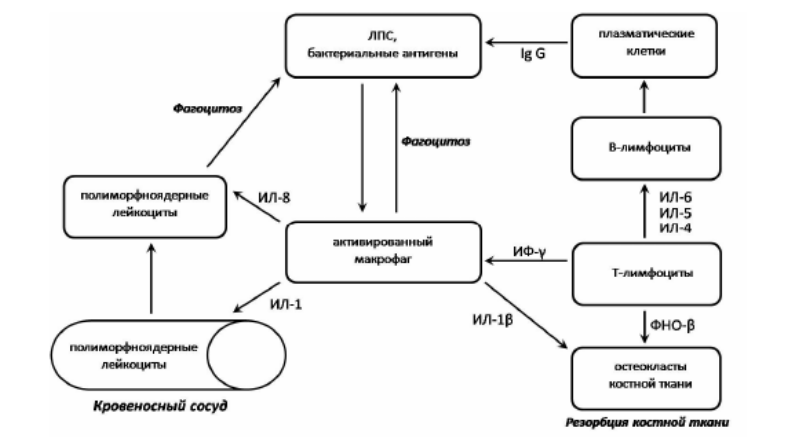

Менструальная кровь – это отличный ресурс железа. Кровянистые выделения не только создают оптимальную рН среду для размножения ряда бактерий и простейших, в том числе трихомонад, но также содержат большое количество эритроцитов, которые легко разрушаются, а поэтому железо становится легко доступным источником питания и размножения для этих микроорганизмов. Если учесть, что в период менструации уровни гормонов (женских и мужских гормонов, прогестерона) понижены, это тоже понижает уровень защиты, несмотря на наличие большого количества разных видов лейкоцитов в тканях матки и других репродуктивных органов.

Менструация – это состояние пониженного иммунитета. Комбинация таких оптимальных условий приводит к активному росту многих бактерий, поэтому нередко обострение половых инфекций возникает в период менструации или же сразу после ее окончания. Интересно, что перед самой менструацией уровень железа во влагалищных выделениях чрезвычайно низкий, что повышает активность микробов-паразитов, а значит, их вирулентность в поисках источников питания.

Хотя кровянистые выделения вымывают часть микрофлоры влагалища и очищают его от «лишних сожителей», трихомонады и другие патологические микробы умеют прикрепляться к клеткам покровного эпителия и использовать появившееся железо быстро и рационально во свое же благо. В лабораторных экспериментах замечено, что у трихомонад, выращенных на средах, не содержащих железа, выработка белков понижается на 80%, а процесс размножения замедляется в 2.5 раза.

Попадая на слизистые оболочки мочеполового тракта, трихомонады фиксируются на клетках плоского эпителия слизистой оболочки и вызывают воспалительный процесс. Трихомонады выделяют во внешнюю среду гиалуронидазу, которая приводит к значительному разрыхлению тканей и проникновению в межклеточное пространство токсичных продуктов жизнедеятельности трихомонад и сопутствующей флоры.

Хотя трихомонады не вызывают воспаление маточных труб, однако они являются кофакторами в передаче, а также в транспорте гонококков, хламидий и других микроорганизмов, которые вовлечены в воспалительные процессы органов малого таза. Риск возникновения непроходимости маточных труб при наличии трихомонад повышается почти в два раза. Если у женщины наблюдаются повторные эпизоды трихомониаза, риск трубного бесплодия повышается в шесть раз.